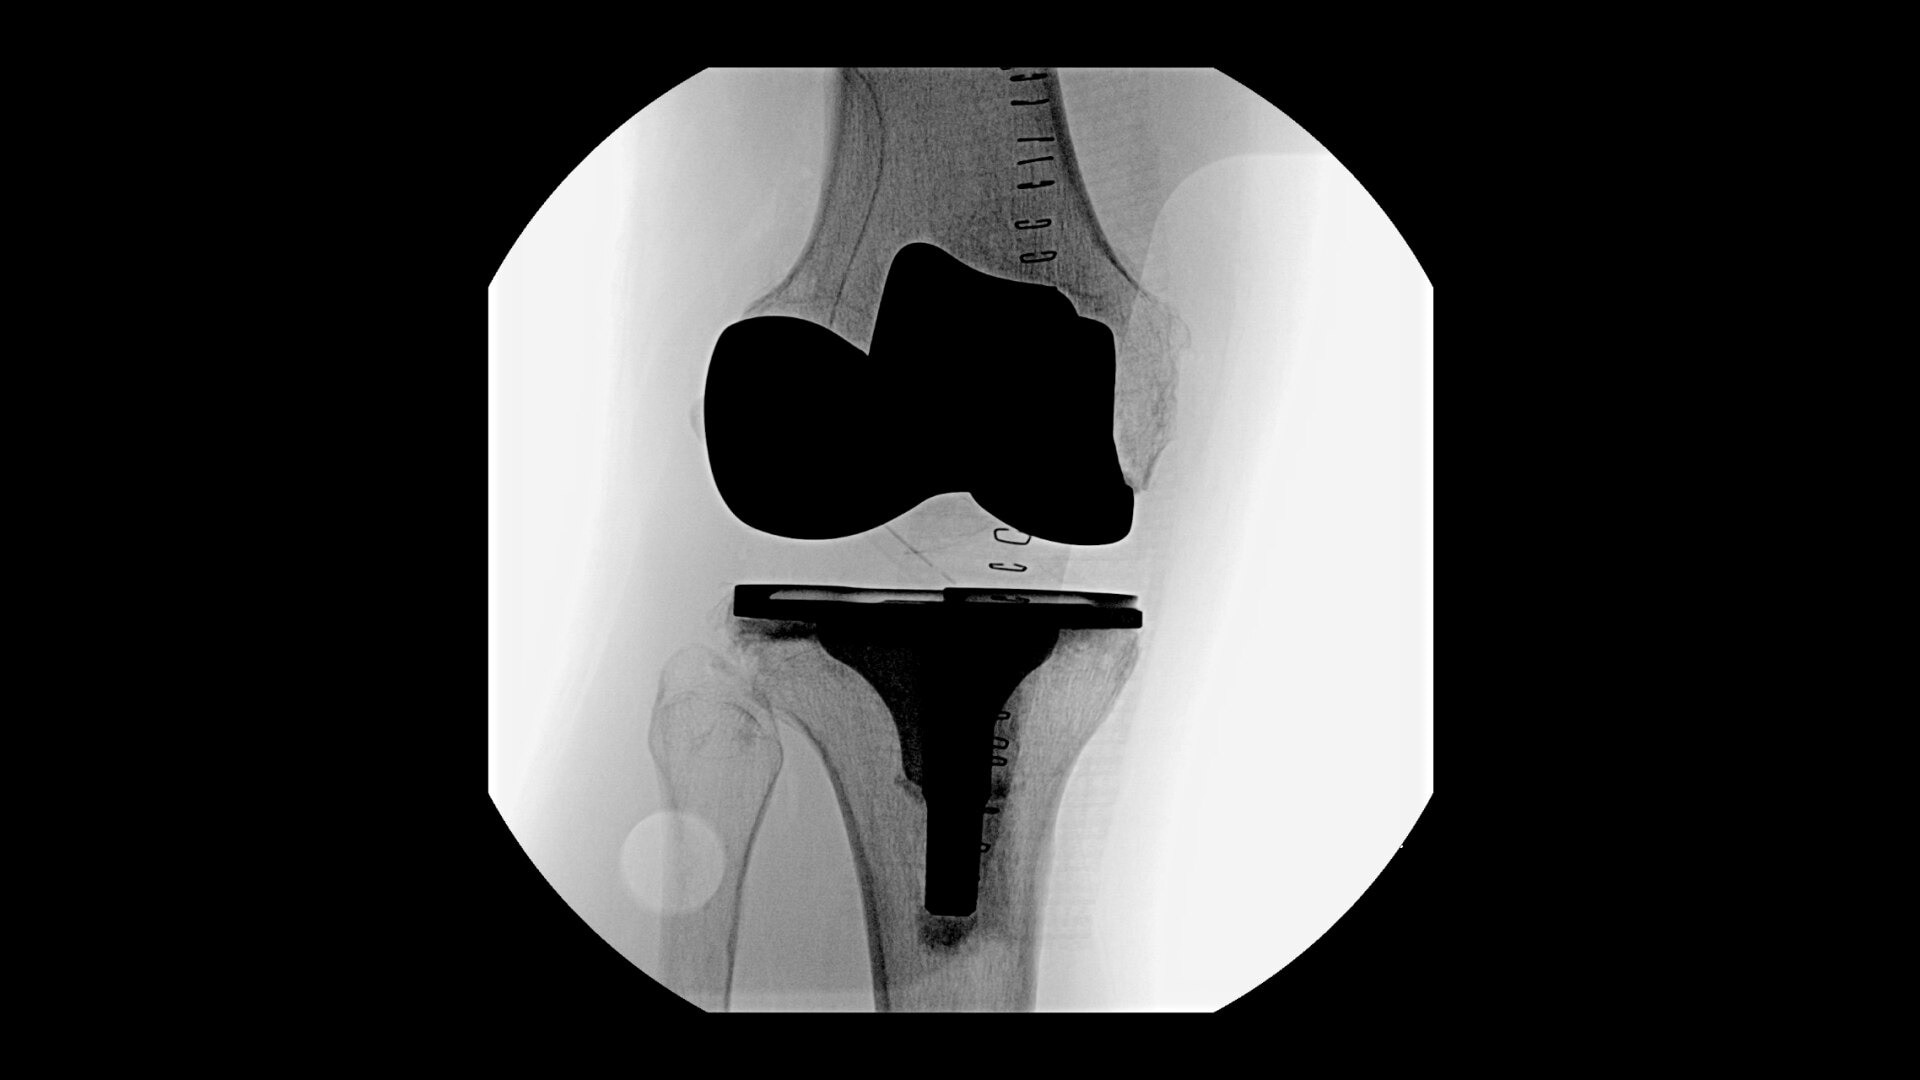

• Knee replacement

Complex orthopedic procedures require powerful imaging systems. OEC premium C-arms perform in a variety of procedures such as:

OEC C-arms provide orthopedic imaging with a large field of view optimized to clearly visualize orthopedic anatomy, such as the entire long bone femur or minute fractures in extremities. A clear display with comfortable viewing can easily show AP and lateral views, enabling efficient procedure planning.

See precise anatomical detail of varying densities such as bone and soft tissue with a high dynamic range with the OEC Elite CFD with a flat detector, image processing advancements and 4K viewing display.